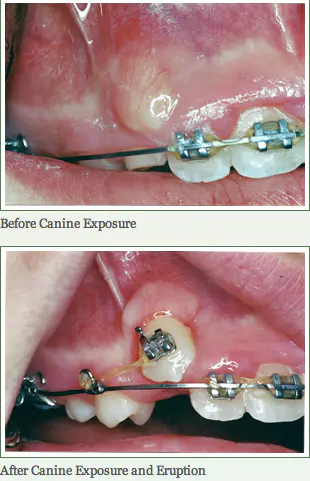

Canine Impactions

Removal of tissue surrounding the impacted tooth to help bring it into the mouth and expedite the orthodontic treatment.